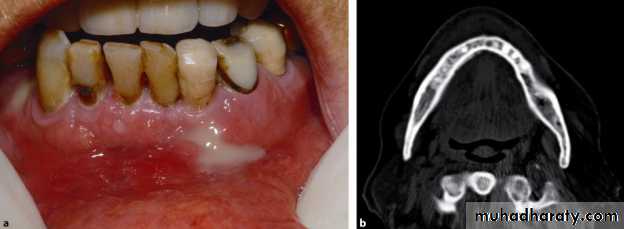

• Old case with advanced chronic osteomyelitis of the left mandible.

• (a) The massive affection of the left mandible demonstrates extraoral fistula• and scar formation.

• (b) Intraoral view of the same patient with large exposure of infected bone and sequestra.

• (c) Large sequester collected from surgery

A patient with a clinically extensive chronic osteomyelitis of the frontal region with multiple fistula and abscess formations.